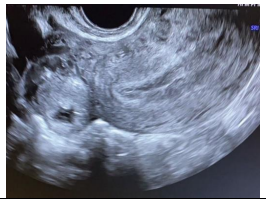

Observe a imagem a seguir.

Sobre as malformações uterinas, os critérios diagnósticos revelados na imagem se correlacionam a qual diagnóstico de malformação mülleriana?